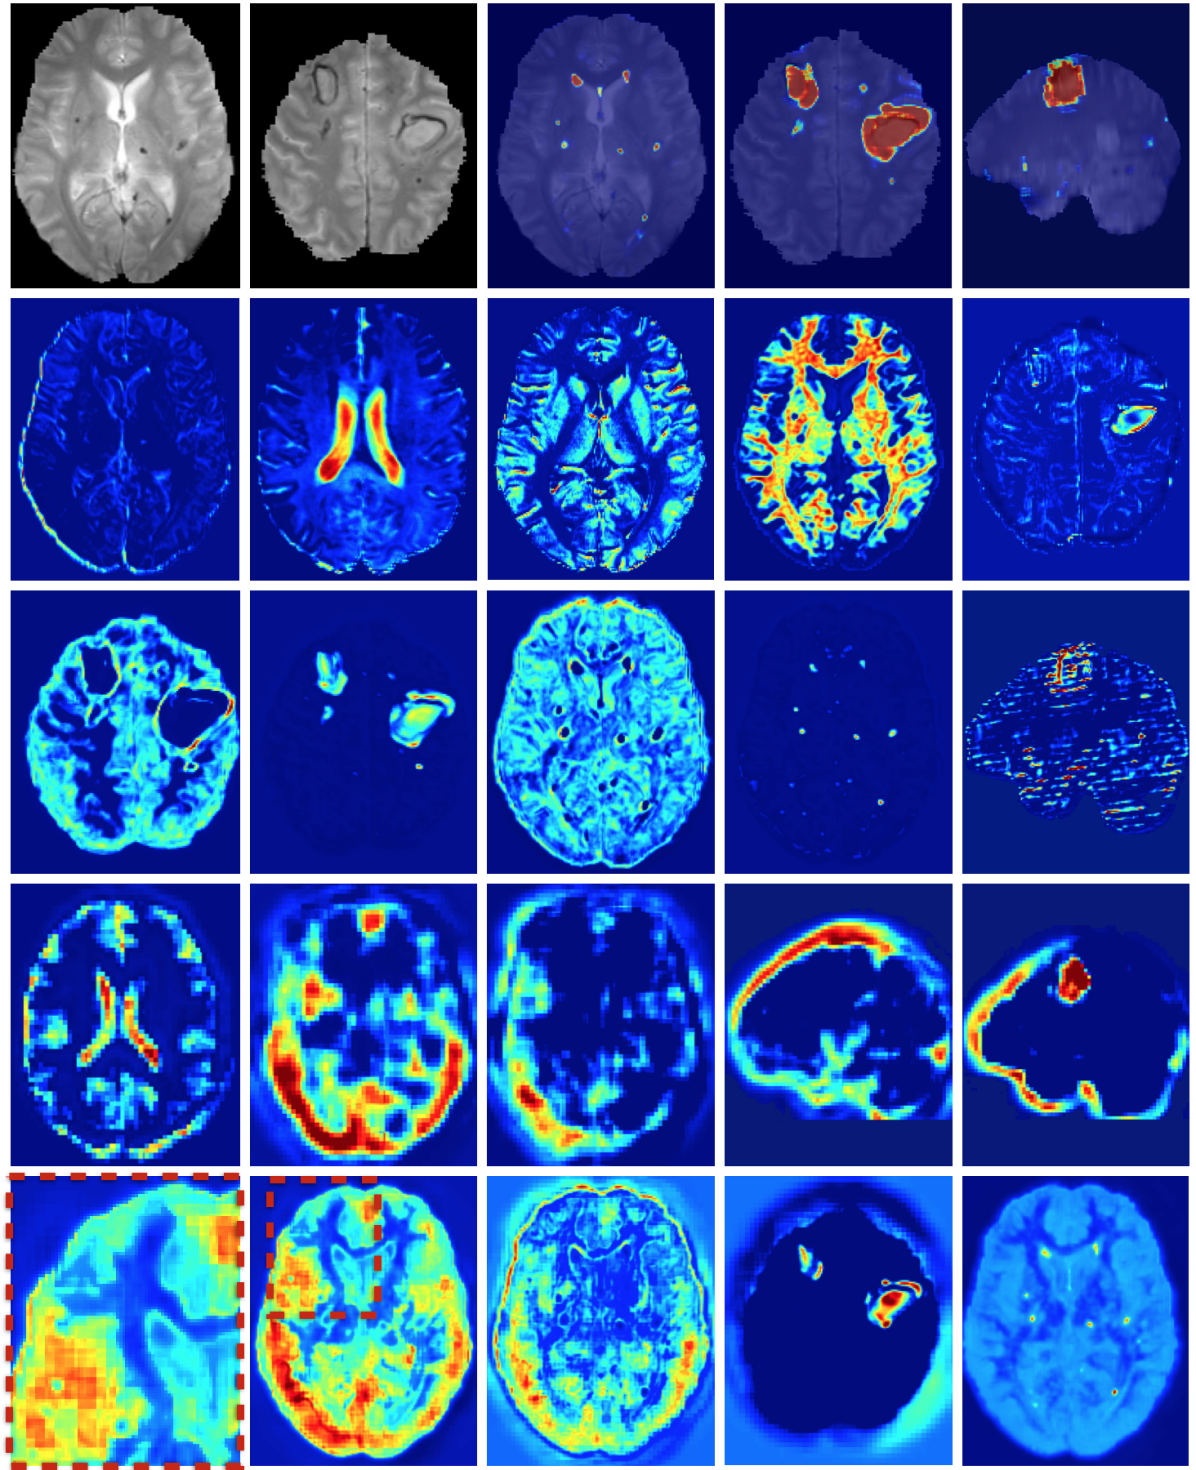

Figure 1 illustrates some of the challenges that arise when devising a computational approach for the task of automatic lesion segmentation. The figure summarizes statistics and shows examples of brain lesions in the case of TBI, but is representative of other pathologies such as brain tumors and ischemic stroke. Lesions can occur at multiple sites, with varying shapes and sizes, and their image intensity profiles largely overlap with non-affected, healthy parts of the brain or lesions which are not in the focus of interest. For example, stroke and MS lesions have a similar hyper-intense appearance in FLAIR sequences as other WMLs (Mitra et al. (2014); Schmidt et al. (2012)). It is generally difficult to derive statistical prior information about lesion shape and appearance. On the other hand, in some applications there is an expectation on the spatial configuration of segmentation labels, for example there is a hierarchical layout of sub-components in brain tumors. Ideally, a computational approach is able to adjust itself to application specific characteristics by learning from a set of a few example images.

Figure 1: Heterogeneous appearance of TBI lesions poses challenges in devising discriminative models. Lesion size varies significantly with both large, focal and small, diffused lesions (a,b). Alignment of manual lesion segmentations reveals the wide spatial distribution of lesions in (c,d) with some areas being more likely than others. (e) shows the average of the normalized intensity histograms of different MR channels over all the TBI cases in our database, for healthy (green) and injured (red) tissue. One can observe a large overlap between the distributions of healthy and non-healthy tissue.